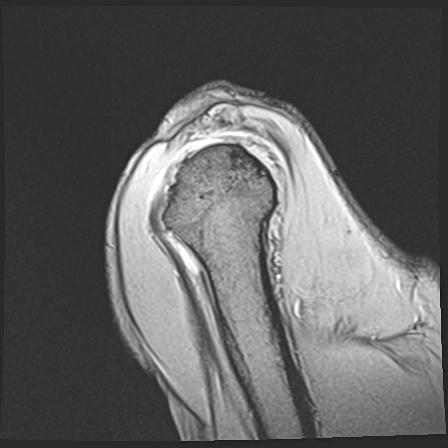

60058 3/9 11/4 右肩 2R+MRI 73歳男性 肩腱板損傷